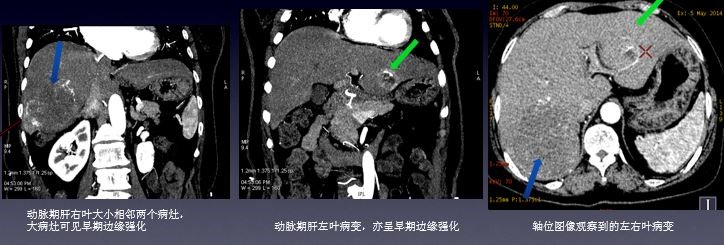

临床资料:女性,66岁,肠道间质瘤术后7个月,常规复查,超声发现肝脏多发病变,为明确病变性质行CT增强能谱扫描。 扫描参数:GSI-22,375mA@0.7sec/rot@DC40mm@SFOV Body Large, pitch 1.375:1 CT印象:

动脉期能谱曲线分析: 肝左叶边缘环状强化部分及肝右叶小病灶具有基本一致的曲线(红/蓝) 肝左叶病灶中心部分与肝右叶大病灶具有较接近的曲线(绿/粉)

门脉期能谱曲线分析: 肝右叶两个病灶能谱曲线接近一致(绿/深蓝) 病灶边缘及内部进一步强化,CT值升高,碘基图碘含量增加

延迟期能谱分析: 左侧病灶CT值及碘含量持续升高 肝右叶两个病灶能谱曲线仍然接近一致

临床分析及诊断: 该患者有肠道间质瘤病史,病灶具有丰富的血供,血供来源一致,能谱分析肝左右叶病灶具有特征相似的能谱曲线,增强后不同于原发肝癌“快进快出”的强化特点,有逐渐延迟强化的趋势,考虑为肝脏的多发转移可能大。该病人于3周后手术治疗,病理结果证实为肠道间质瘤的多发肝转移。 小结:能谱曲线可更加直观的从病灶动脉期强化程度及持续时间对肝脏富血供占位进行鉴别,应用强化前后能谱曲线的高度和斜率变化来评估病变的血供特点,结合血管显示的最佳keV图像,可从多个角度反映病变特征,达到诊断和鉴别诊断的目的。 临床小知识: 胃肠道间质瘤(Gastrointestinal Stromal Tumors, GIST)是一类起源于胃肠道间叶组织的肿瘤,占消化道间叶肿瘤的大部分。Mazur 等于1983 年首次提出了胃肠道间质肿瘤这个概念。胃肠道间质瘤占胃肠道恶性肿瘤的1~3%,多发于中老年患者,GIST大部分发生于胃(50~70%)和小肠(20~30%),结直肠约占10~20%,食道占0~6%,肠系膜、网膜及腹腔后罕见。GIST病人20-30%是恶性的,第一次就诊时约有11~47%已有转移,转移主要在肝和腹腔。手术切除是胃肠道间质肿瘤首选且唯一可能治愈的方法,GIST高危患者术后复发转移率高,可达55%~90%,80%在术后1~2年内有3/4局部复发。 致谢:辽宁省瓦房店市中心医院